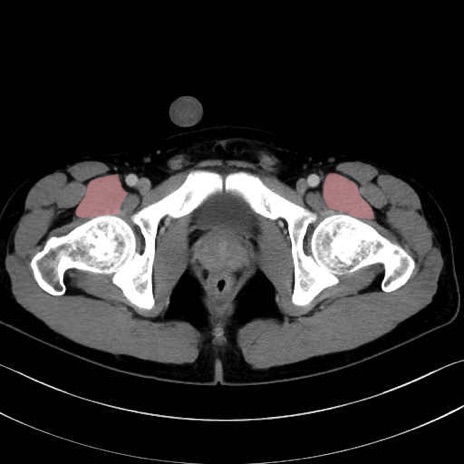

腸骨筋 (Iliacus)